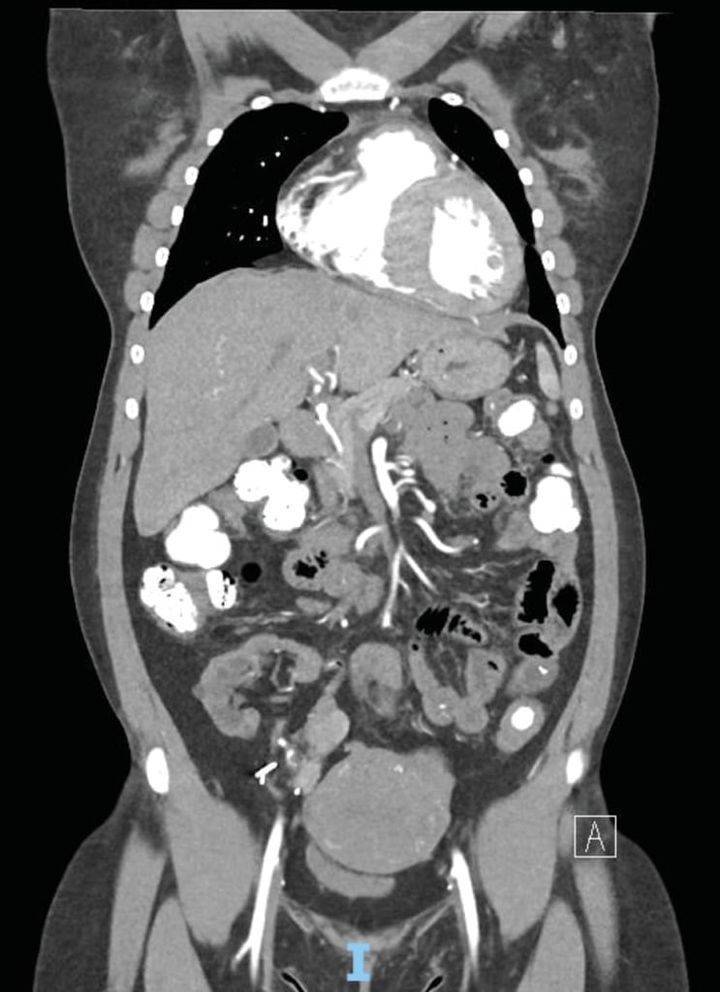

女性患者のCT画像、大腸が摂取した粘土(白)で膨れ上がっていた/ Credit: Archit V. Potharazu et al., Annals of Internal Medicine: Clinical Cases(2025)

検査用のCT画像では、大腸全体に高密度の物質が映し出され、粘土の影響で出血源を見つけるのも困難だったといいます。